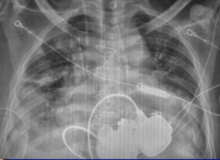

Carmelo Milano, chief of cardiac surgery and the surgical director of the left ventricular assist device (LVAD) program at Duke University Medical Center in Durham, North Carolina, USA, discusses the current practice of destination therapy LVAD and future perspectives of mechanical circulatory support.